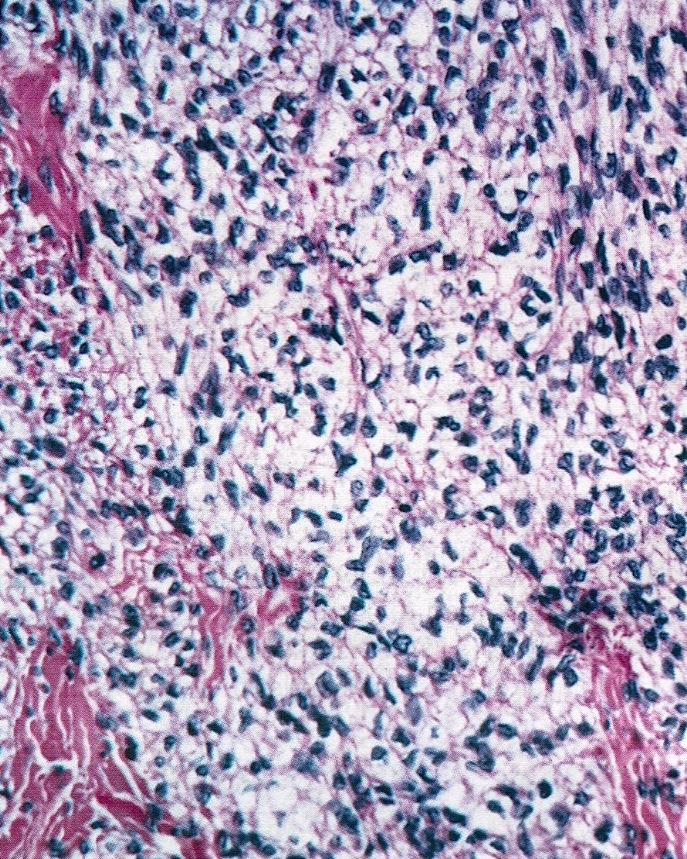

Microscopic (histologic) description

- Predominant population of cells showing ovoid to round nuclei and pale gray cytoplasm, which can be abundant

- Minor component of the tumor may have spindled nuclei, reflecting overlap between fibroma and thecoma

- Indistinct cell membranes impart a syncytial appearance

- Diffuse or nodular growth pattern

- Absent or minimal nuclear atypia

- Mitotic rate usually < 5/10 high power fields

- Hyaline plaques

- Cytoplasmic lipid vacuoles may be present but are not essential

- May show aggregates of cells with brightly eosinophilic cytoplasm (lutein cells)

- Calcification is more common in young patients (Int J Gynecol Pathol 1988;7:343)

- Uncommon features include keloid-like sclerosis, nuclear grooves, bizarre nuclear atypia (Am J Surg Pathol 2014;38:1023)

- Rarely contains a minor component of sex cord elements (Int J Gynecol Pathol 1983;2:227)

- Malignant thecoma: very rare, diagnosis requires diffuse moderate to severe nuclear atypia and high mitotic rate (> 4/10 high power fields) (Am J Surg Pathol 2011;35:e15)

Microscopic (histologic) images

Contributed by Victoria Collins, M.D., Tamara Kalir, M.D., Ph.D., AFIP and @SeoparjooAzmel on Twitter